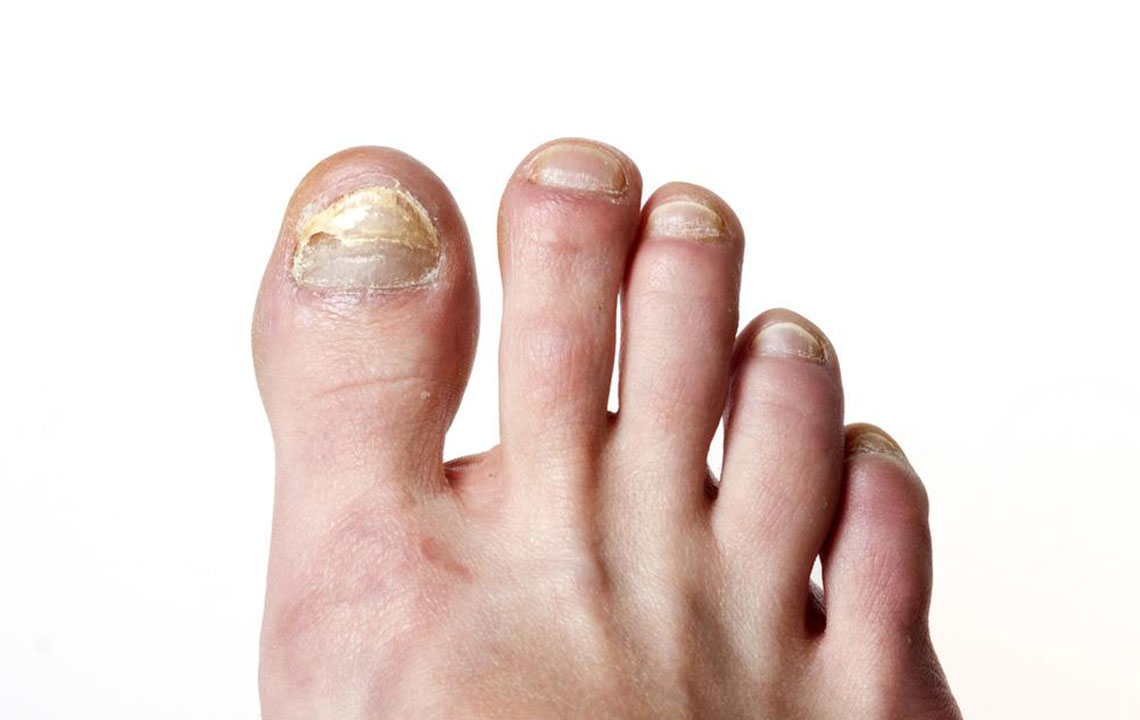

Tried and Tested Natural Cure for Toenail Fungus

Onychomycosis, which is usually known as toenail fungus is characterized by pain, inflammation, swelling, thickening, yellowing and crumbling of the nail. Most common reasons for toenail infection include abnormal skin pH level, synthetic socks, exposure to moisture, poor foot hygiene, sweat build-up in shoes, compromised immune system, and weak circulation due to diabetes.